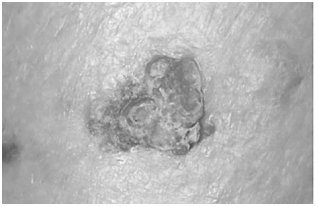

A imagem abaixo mostra uma lesão localizada

na região malar direita de um idoso trabalhador

rural do Vale do São Francisco:

Um homem de 76 anos, trabalhador rural desde a juventude, procura atendimento devido a uma lesão facial que vem aumentando de tamanho nos últimos meses. Refere queimaduras solares repetidas, nunca fez uso regular de protetor solar e tem múltiplas áreas de queratose actínica.

Ao exame, observa-se lesão hiperqueratótica e ulcerada, de bordas endurecidas de 1,8cm. Não há linfonodos cervicais palpáveis.

A alternativa CORRETA é: